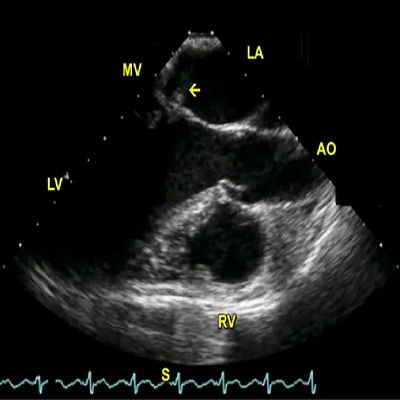

Arrow in point to false tendon